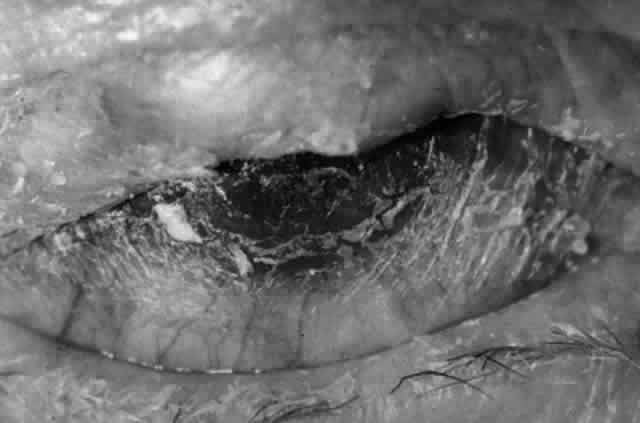

CICATRICIAL PEMPHIGOID

Cicatricial pemphigoid (CP) is a chronic cicatrizing autoimmune disease of the mucous membranes and skin. It is said to have an average age of onset of 65 years, but this figure under-reports the true epidemiologic features of this disease, because the cases are usually not in their earliest stages.17 Females are affected two to three times as frequently as males. Conjunctival involvement may occur as early as 10 years before other mucosal or skin lesions develop, or it may occur as late as 20 years after the onset of other lesions; the disease may be limited to the conjunctiva (Fig. 5). The scarring Brusting-Perry dermatitis occurs in approximately 25% of cases (Fig. 6), and cicatrizing conjunctivitis develops in 70% to 75%.17,18 Involvement of other mucosa may lead to scarring of the soft palate and oral and nasal mucosa, and esophageal, urethral, vaginal, and anal strictures may develop. Laryngeal involvement may cause pain and hoarseness,19 and the esophageal scarring can be lethal, because asphyxiation can result from a food bolus that is lodged during attempted swallowing by a patient with dysphagia from esophageal strictures that have been neglected by patient and physician alike.

Fig. 5. Eye of a patient with cicatricial pemphigoid, biopsy-proven, without extraocular manifestations. The disease has progressed to end stage and blindness. Note the total “leatherization” of the eye, with complete adherence of the eyelids to the globe.